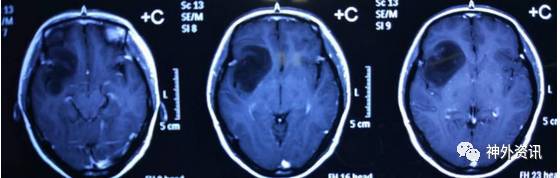

4. 影像学检查如下:

术前MR

术前波谱